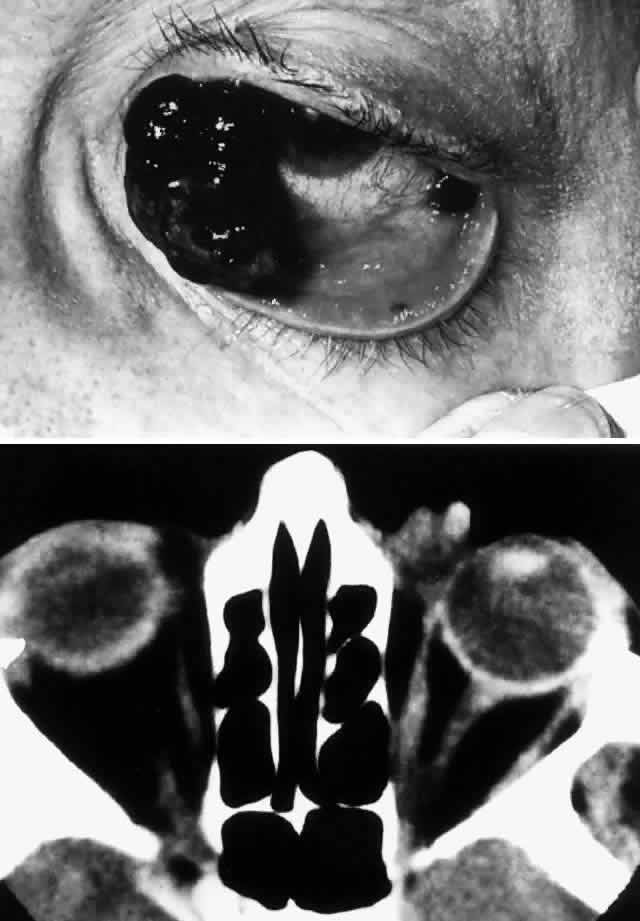

Fig. 2. A 32-year-old woman presented with a 1-month history of sinus congestion and nasal obstruction unresponsive to antibiotics. In the 1 week preceding the initial exam, the right eye became progressively more prominent and showed tearing and redness. On examination, there was mild edema of the lower lid and dysesthesia in the distribution of cranial nerve V2, and the globe was displaced 6 mm laterally and 5 mm anteriorly. There was mild limitation of abduction, chemosis, and nasal choroidal folds. An axial CT scan revealed a diffuse, destructive soft tissue mass centered in the superior nasal passage and ethmoid sinuses extending into the right orbit in contiguity with the medial rectus (A). On enhanced coronal view, the tumor was noted to involve the right maxillary antrum and to extend superiorly into the anterior cranial fossa (B). Biopsy of the sinus (C) revealed an alveolar-type rhabdomyosarcoma (muscle stain, × 320).

Fig. 3. A 73-year-old man presented with a 2-year history of infraorbital numbness and burning sensation, which had progressed to include the supraorbital region, forehead, and lower face during the past 6 months. He had been treated with radiotherapy for prostate carcinoma 7 months before orbital presentation. Examination was significant for proptosis of 2 mm and dysesthesia, including corneal numbness, in all three divisions of cranial nerve V. CT scan revealed a soft tissue mass in the inferior orbit contiguous with the inferior rectus muscle (A). The lesion extended through the infraorbital canal to involve the pterygopalatine fossa and was associated with soft tissue hanging into the upper portion of the maxillary sinus. An axial CT scan-guided aspiration biopsy was performed (B) and revealed squamous cell carcinoma. Groups of cohesive malignant squamous epithelial cells (C) were noted to have pleomorphic nuclei and abundant eosinophilic to orange cytoplasm, with no features of mucinous differentiation (H & E, × 320). (C from White VA, Rootman J: Orbital pathology. In Albert DM, Jakobiec FA (eds): Principles and Practice of Ophthalmology, Vol 4, p 2342. Philadelphia, WB Saunders, 1994.)